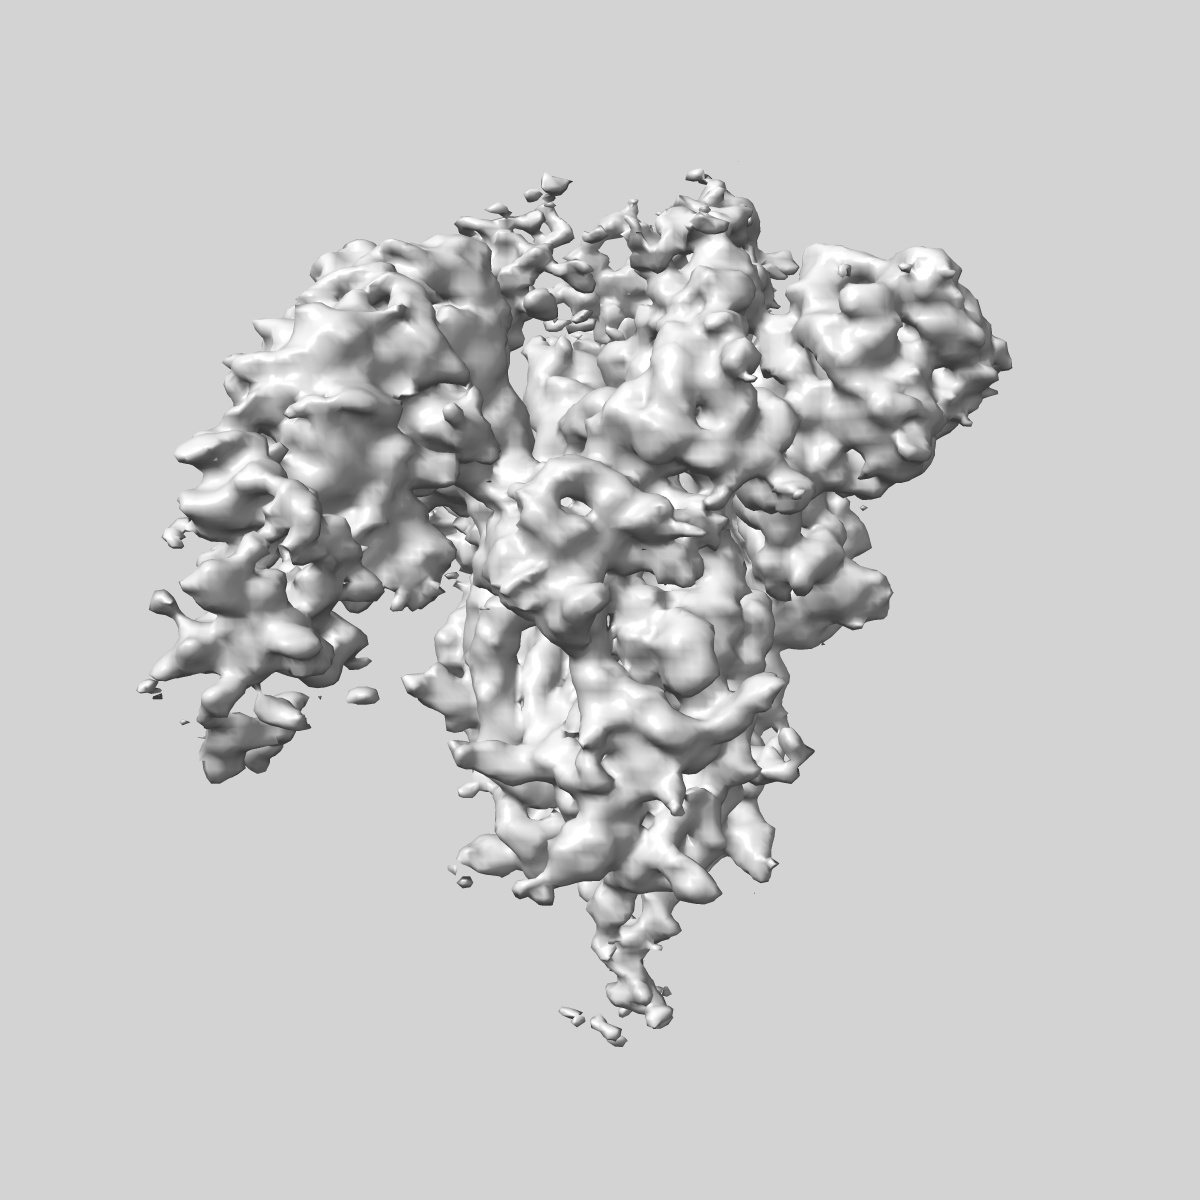

EMD-48198

SARS-CoV-2 Delta Spike ectodomain in complex with human polyclonal antibody ModDe-NTD1 (mRNA-1273 vaccine)

Single-particle4.3 Å

Sample: SARS-CoV-2 Delta spike ectodomain in complex with human polyclonal antibody ModDe-NTD1